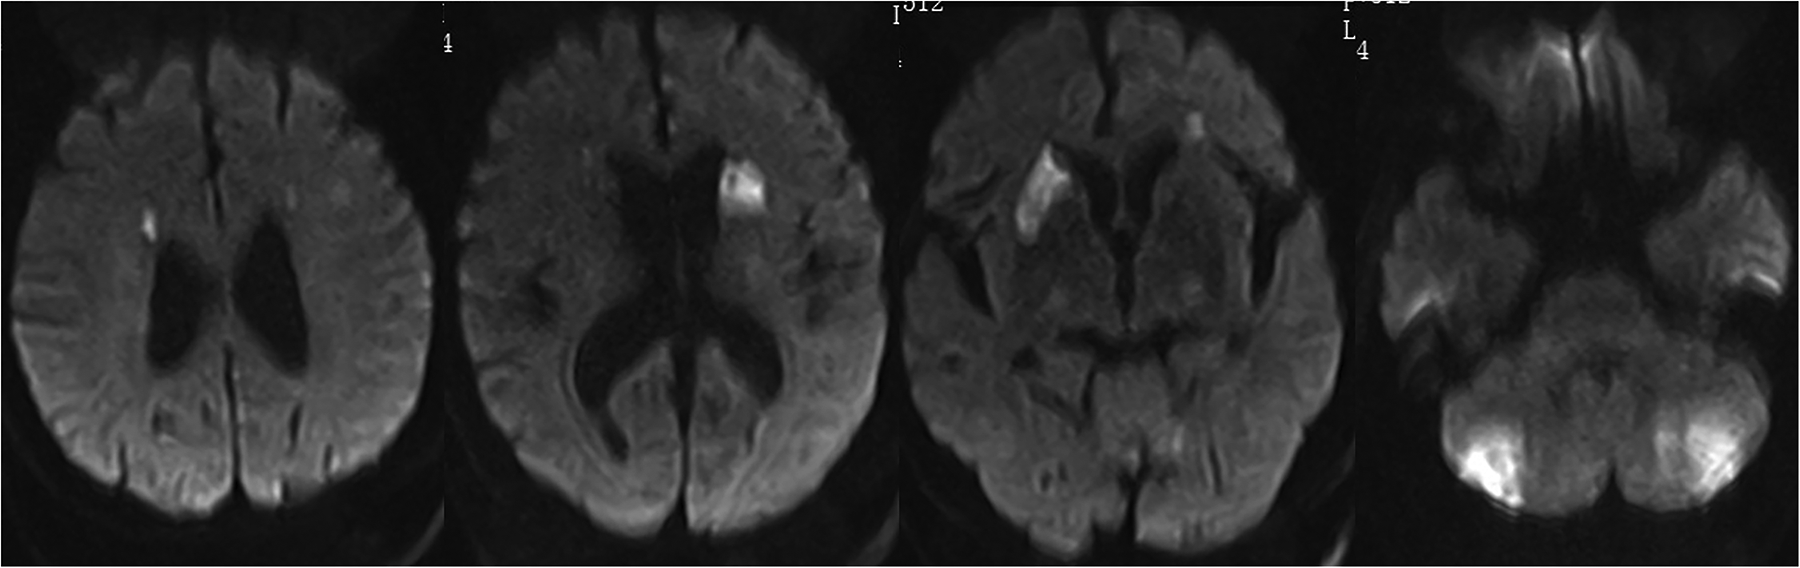

Despite cefoperazone-sulbactam therapy, the patient continued to have fever and rising inflammatory markers. He experienced intermittent limb weakness and delirium, resolved spontaneously after lasting for several minutes. On the 7th day, Magnetic Resonance Imaging Diffusion-Weighted Imaging (MRI DWI) revealed multiple acute cerebral infarctions and lacunar infarcts (Figure 2). Aspirin and clopidogrel were added, but he later developed coma and respiratory failure, necessitating intubation and Intensive Care Unit admission.

Figure 2

MRI DWI shows multiple acute infarctions in the bilateral periventricular regions, basal ganglia, and cerebellum, with a few lacunar infarctions in the bilateral frontal and parietal lobes.